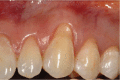

Gingival recession is an oral health problem that affects a large part of the population. Several treatments are suggested in the current literature; among them is the use of buccal fat pad grafting. The objective of this case report is to describe the treatment of a Miller Class I gingival recession using a nonpedicled buccal fat pad graft immediately after performing the surgery for buccal fat pad removal (bichectomy technique). First, bilateral surgical removal of the buccal fat pad was performed with the main objective of eliminating oral mucosa biting. The recipient site was prepared to receive a portion of the fat pad that was cut and macerated in a size that was sufficient to cover the recession. The patient was followed up at 15, 30, 60, and 365 days postsurgery, and the results showed an elimination of the oral mucosa biting and complete coverage of the gingival recession. It was concluded that the nonpedicled buccal fat pad graft is another option for the treatment of Miller Class I recessions.